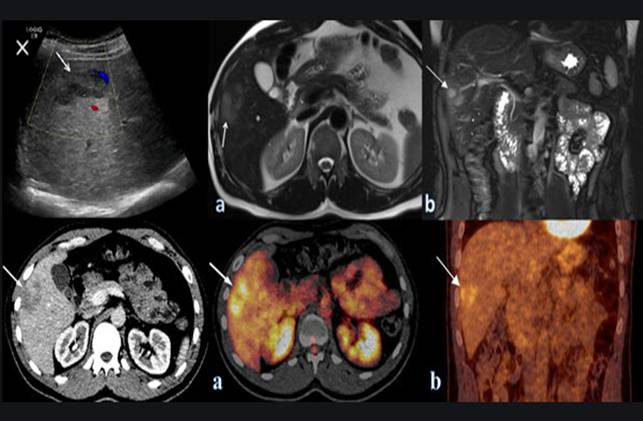

Một phụ nữ 48 tuổi phàn nàn có sự khó chịu ở vùng bụng, bệnh nhân chưa từng có các triệu chứng như vậy trước đó, biểu hiện đau ra sau lưng và cảm giác đầy bụng. Các triệu chứng của bệnh nhân đã liên tục tăng trong 5 năm qua. Bệnh nhân này đã mất sụt mất 12 pounds trong vòng 6 tháng qua. Đồng thời, bệnh nhân buồn nôn và biếng ăn/ chán năn. Đầu tiên, bệnh nhân được đưa vào một bệnh viện, sau đó siêu âm bụng và chụp cắt lớp vi tính ổ bụng (CT-scanner) được thực hiện. Siêu âm cho thấy một khối thương tổn [38 × 29 mm]. Các hình ảnh CT-scanner xác nhận phát sự hiện diện của khối này bằng cách tìm ra được một khối [3 × 4 cm] giảm dần đậm độ về trung tâm, tổn thương ở thùy trái của gan. Ngoài ra, ở vùng rốn gan, có hạch bạch huyết 31 mm đã được xác định.

Các nghiên cứu hình ảnh được lặp lại sau đó nhiều lần sau khi hội chẩn của cả nhóm. Những hình ảnh CT-scanner trước khi điều trị ban đầu cho thấy có khối rắn nhạt màu dần dần về trung tâm [7 × 5,5 cm] trong các phân thùy gan 2, 3 và 4. Các khối u cũng được tìm thấy, gây ra tắc mật ở thùy trái. Hơn nữa, hạch đã được xác định, với các hạch bạch huyết lớn nhất là 2,7 cm, đường kính trong khu vực khoang tĩnh mạch. Một xét nghiệm máu tổng thể đã được thực hiện cho thấy BCAT (2.900/mm3), chính chỉ số này gợi ý dẫn tới sự nghi ngờ của một ca bệnh nhiễm ký sinh trùng. Để cho ra một chẩn đoán xác định, nhóm nghiên cứu đã thực hiện sinh thiết. Trong việc kiểm tra bệnh lý, tổn thương một phần hình thành u hạt đó bao gồm toàn bộ BCAT và rất ít tế bào đơn nhân được xác định.

H3

Trong nhu mô gan, hình ảnh thương tổn do sán đã được xác định. Với một chẩn đoán phân biệt là ca bệnh nhiễm sán lá gan lớn Fasciola hepatica, huyết thanh chẩn đoán miễn dịch theo phương pháp và kỹ thuật (Fast enzyme-linked immunosorbent assay_FAST-ELISA) đã thực hiện nhằm thiết lập chẩn đoán cuối cùng. Sau khi chẩn đoán xác định, chỉ định liệu pháp điều trị sán lá gan lớn bằng triclabendazole (TCBZ) được chỉ định. Bệnh nhân sau đó được ra viện và yêu cầu tái khám 3 tháng sau để theo dõi diễn tiến. Kết quả của một CT-scanner khác sau đó cho thấy sự phục hồi cả khối u và các hạch lympho rõ ràng trên hình A và B.

Các chẩn đoán hình ảnh thấy chụp CT-scanner ổ bụng kiểm tra cho thấy một khối thương tổn giảm âm, giảm dần độ đậm về trung tâm 7 × 5,5 cm trong nhu mô gan. Sau đó, hình ảnh CT scanner khác cho thấy sự phục hội và xóa mờ các “khối u” ở trong nhu mô gan. Sinh thiết gan được đánh giá đối với u có tăng BCAt và cấu trúc nhu mô và giải phẩu bệnh giống như thương tổn do ký sinh trùng.